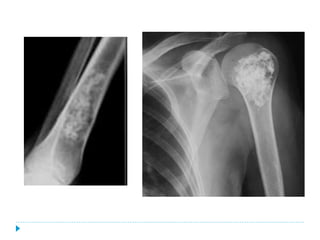

![ENCONDROMA

Grupos de edad:

20-40 años

Genero:

♂1:1♀

Ubicación:

Falanges [60%]

Fémur [16%]

Húmero proximal [7%]

CONDROMA PERIOSTAL

20-30 años

♂2:1♀

Húmero proximal [50%]

Metacarpianos

Falanges](https://image.slidesharecdn.com/condroma-150104112721-conversion-gate02/85/Condromas-3-320.jpg)